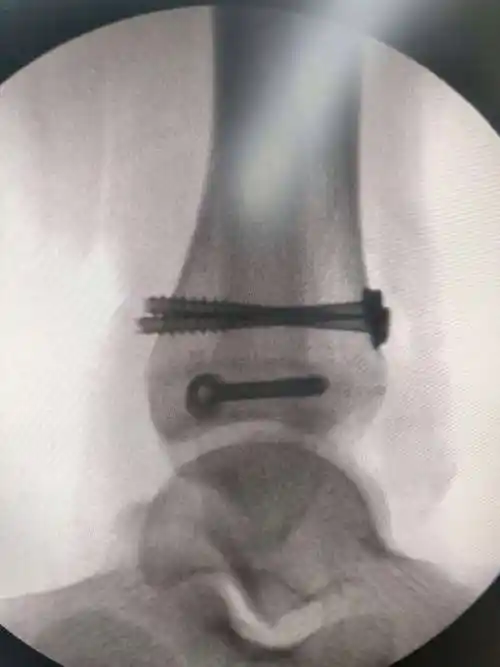

股骨中下段骨折倒打钉内固定